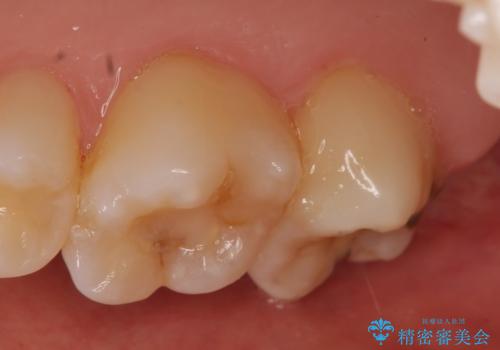

- 冷たいものを飲むと右上の奥歯がしみるので診て欲しいといらっしゃった方の症例です。

右上6番目、7番目の歯の樹脂が劣化していたため、虫歯除去後セラミックインレーによる修復を行いました。